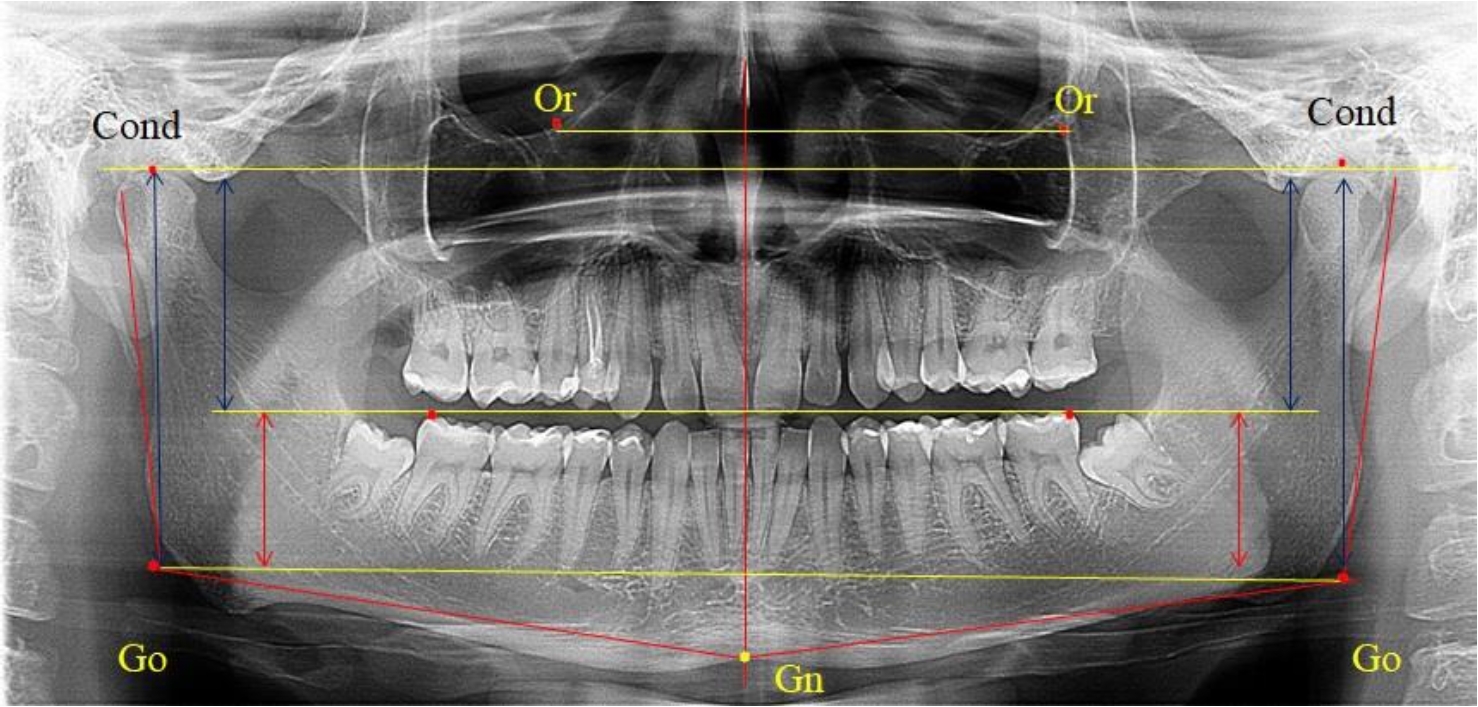

На боковых телерентгенограммах определяли положение верхней точки суставной головки Cond. Касательные линии к ветви и телу нижней челюсти пересекались в точке, которую в клинической практике обозначают как точка угла нижней челюсти или точка гонион Go. Точкой hPOcP обозначали дистальный бугорок нижнего второго моляра вблизи окклюзионного контура коронки, через нее от межрезцовой точки проводили окклюзионную линию, ее продолжали до задней части ветви челюсти. Высоту ветви измеряли как расстояние от угла нижней челюсти до вершины суставной головки Go-Cond. Общую высоту ветви условно делили на 2 части, ее границей служила окклюзионная линия. Верхнюю часть обозначали как окклюзионно-суставная, а нижнюю – как окклюзионно-гониональная.

На ортопантомограмме использовали аналогичные суставные точки Cond на каждой стороне, их соединяли между собой суставной линией Cond-Cond.

Касательная к ветви нижней челюсти соединяла выступающие точку. При построении касательной к телу челюсти проводили в обе стороны линии от точки Gn, расположенной в нижней центральной части подбородочного симфиза, до выступающей нижней точки угла челюсти. Касательные линии при пересечении определяли конструктивную точку гонион Go. Соединение гониональных точек определяло положение гониональной линии Go-Go. При соединении окклюзионных точек hPOcP получали окклюзионную горизонталь (рис. 1). Измеряли расстояние между горизонталями в области ветвей нижней челюсти. Статистический анализ проводили в программе Microsoft Excel. Составляли вариационные ряды с последующим расчетом среднего значения, стандартного отклонения и ошибки среднего ±m. Также оценивали максимальные и минимальные значения величин. Определи относительные величины соотношения верхней и нижней частей ветви нижней челюсти.

Рис. 1. Метод измерения высоты ветви нижней челюсти на телерентгенограмме (а) и ортопантомограмме (б)